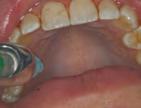

Paciente masculino de 23 años de edad el cual acudió al servicio de Odontología para valoración odon tológica anual como parte del exa men médico anual quien refiere a Cirugía Maxilofacial del Hospital Regional Naval de Acapulco (Figura 1). El paciente mencionó inicio de padecimiento con aumento de volu men y úlcera en paladar blando de 6 meses de evolución con salida de

material purulento (Figura 1). Negó crónico degenerativo, alérgicos y res to de antecedentes sin importancia. Se solicitaron estudios de laboratorio prequirúrgicos los cuales se encontra ron dentro de los parámetros norma les.

Estudios tomográficos en los cuales se observa tumoración expansiva a piso nasal de 3 centímetros de diá metro aproximadamente isodensa a tejidos blandos en zona de pala dar blando (Figura 3A y 3B). Motivo por el cual se decidió realizar biopsia incisional (Figura 4A , 4B y 4C) obte niendo un diagnóstico de Adenocar cinoma de células basales en paladar blando (Figura 5) con el cual se rea lizó referencia al centro oncológico naval para su seguimiento y trata miento. Actualmente se encuentra en tratamiento de quimioterapia.

Paciente Figura 1. Fotografía clínica frontal. Figura 2. Con aumento de volumen y úlcera en paladar blando.